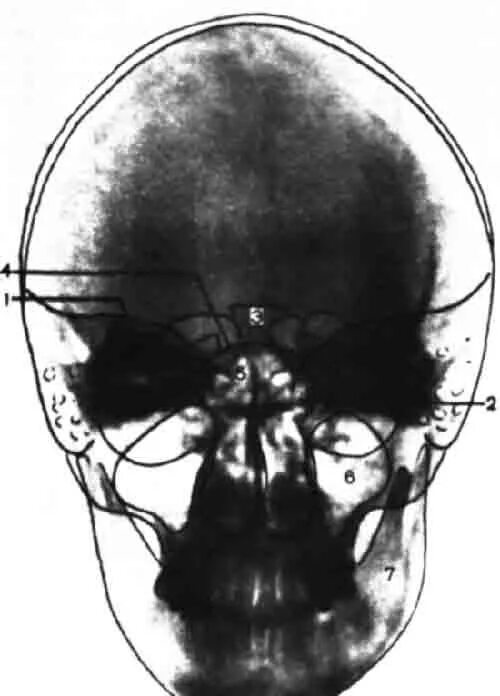

Снимок черепа в прямой проекции